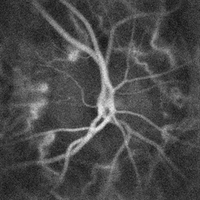

Ophthalmoscopy photograph showing the optic disc as a bright area on the right where blood vessels converge. | |

القرص البصري أو رأس العصب البصري هو نقطة الخروج لمحاور الخلايا العقدية التي تغادر العين . نظرًا لعدم وجود خلايا عصوية أو خلايا مخروطية تغطي القرص البصري ، فإنه يتوافق مع نقطة عمياء صغيرة في كل عين.

تشكل محاور الخلايا العقدية العصب البصري بعد مغادرتها للعين. يمثل القرص البصري بداية العصب البصري وهو النقطة التي تتجمع فيها محاور الخلايا العقدية للشبكية. القرص البصري هو أيضًا نقطة دخول الأوعية الدموية الرئيسية التي تغذي شبكية العين.[1] يحمل القرص البصري في العين البشرية العادية 1 - 1.2 مليون من الألياف العصبية الواردة من العين باتجاه الدماغ .

يتم وضع القرص البصري من 3 إلى 4 مم للجانب الأنفي من النقرة . إنه شكل بيضاوي عمودي ، بمتوسط أبعاد 1.76 مم أفقيًا بنسبة 1.92 مم رأسياً. .[2] وجد انخفاض مركزي متغير الحجم يسمى الكأس البصري . يمكن أن يكون هذا الانخفاض مجموعة متنوعة من الأشكال من المسافة البادئة الضحلة إلى وعاء الفول - يمكن أن يكون هذا الشكل مهمًا لتشخيص بعض أمراض الشبكية.